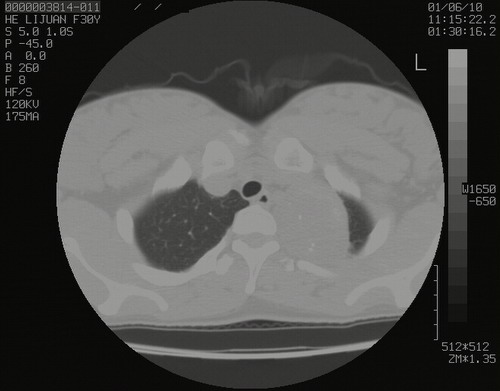

怀孕3个月时(2009-3至4月间),自述突感左侧前后胸疼痛1天,以前胸明显,随后偶感闷痛,余未见异

左肺尖脊柱旁沟肿块,境界清楚,边缘光滑,密度不均,内有多发点片状钙化,考虑良性肿瘤,骨软骨瘤或神经源性肿瘤可能,肺错构瘤不除外。

左后上纵隔见一类圆形肿块影,外侧边界清,密度不均匀,内可见点状钙化影,增强呈不均匀强化,考虑神经源性肿瘤可能。期待病理结果。